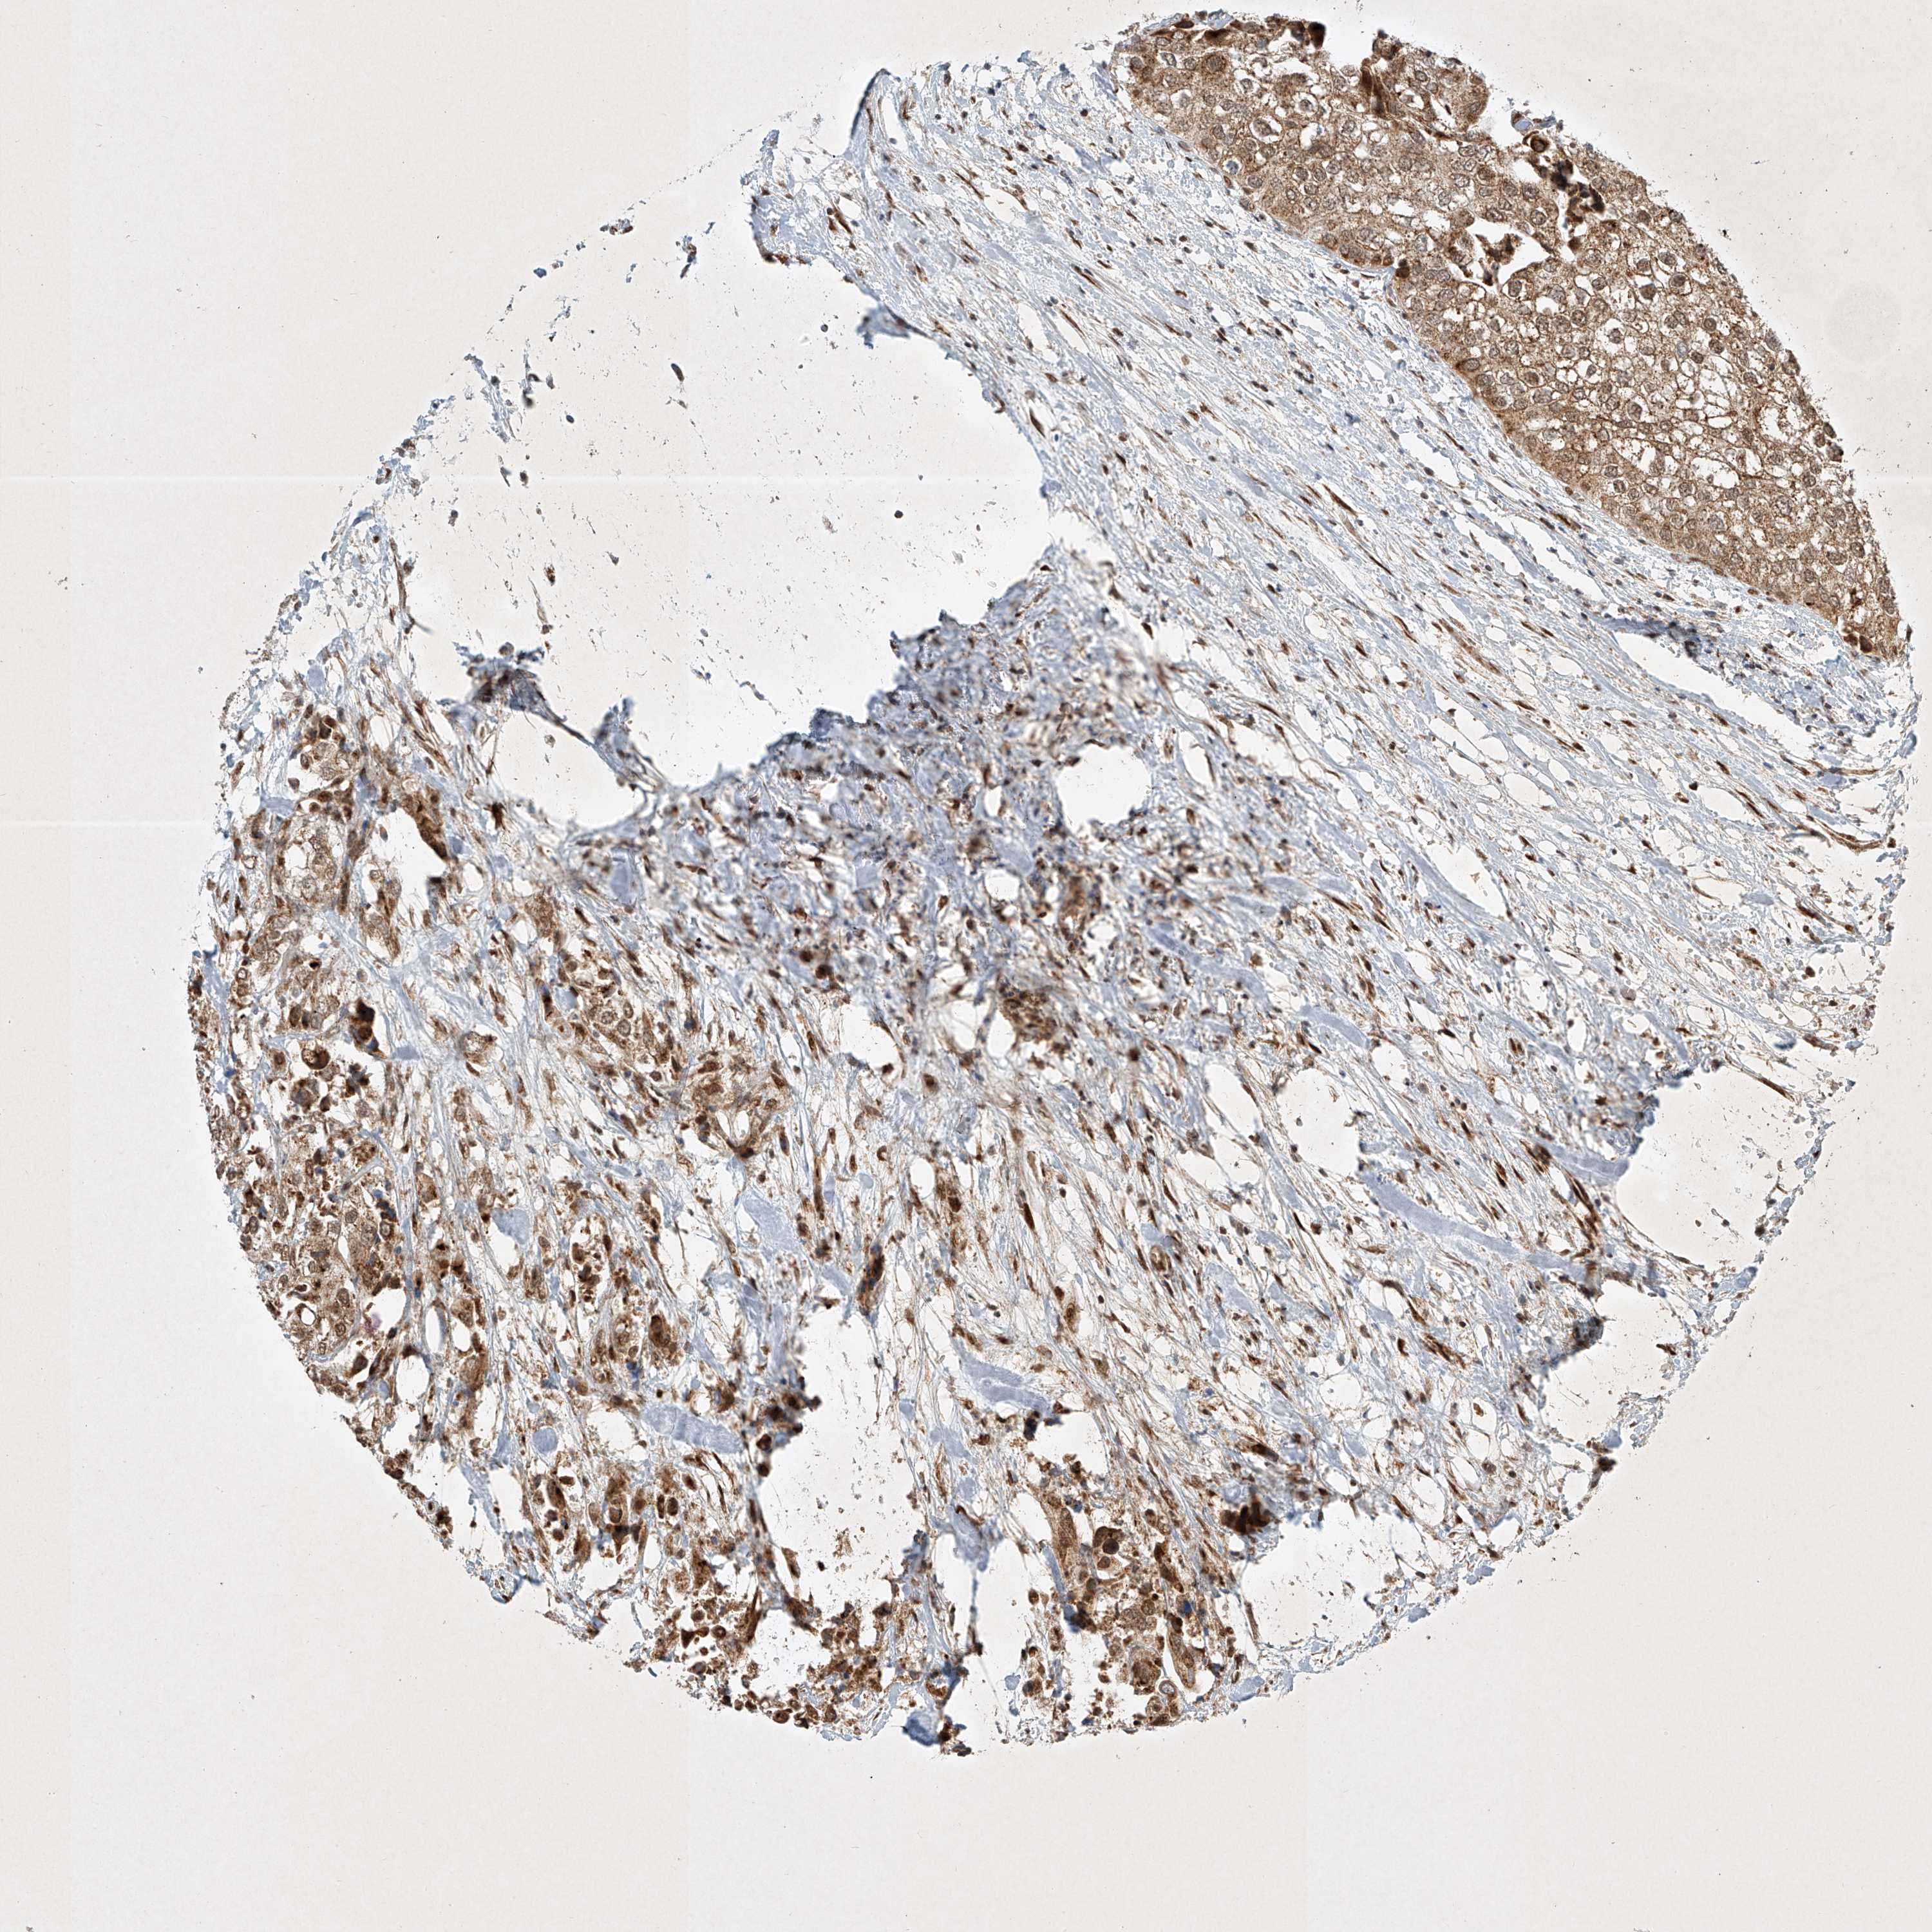

UROTHELIAL CANCER - Protein expressioni

A mouse-over function shows sample information and annotation data. Click on an image to view it in a full screen mode. Samples can be filtered based on level of antibody staining by selecting one or several of the following categories: high, medium, low and not detected. The assay and annotation is described here.

Note that samples used for immunohistochemistry by the Human Protein Atlas do not correspond to samples in the TCGA dataset.

Antibody stainingi

Antibody staining in the annotated cell types in the current human tissue is reported as not detected, low, medium, or high, based on conventional immunohistochemistry profiling in selected tissues. This score is based on the combination of the staining intensity and fraction of stained cells.

Each image is clickable and will lead to virtual microscopy that enables deeper exploration of all samples and also displays staining intensity scores, fraction scores and subcellular localization as well as patient and tissue information for each sample.

Antibody HPA031689

Staining

High

Medium

Low

Not detected

Intensity

Strong

Moderate

Weak

Negative

Quantity

>75%

75%-25%

<25%

None

Location

Nuclear

Cytoplasmic/membranous

Cytoplasmic/membranous,nuclear

Urothelial carcinoma, High grade

Urothelial carcinoma, Low grade